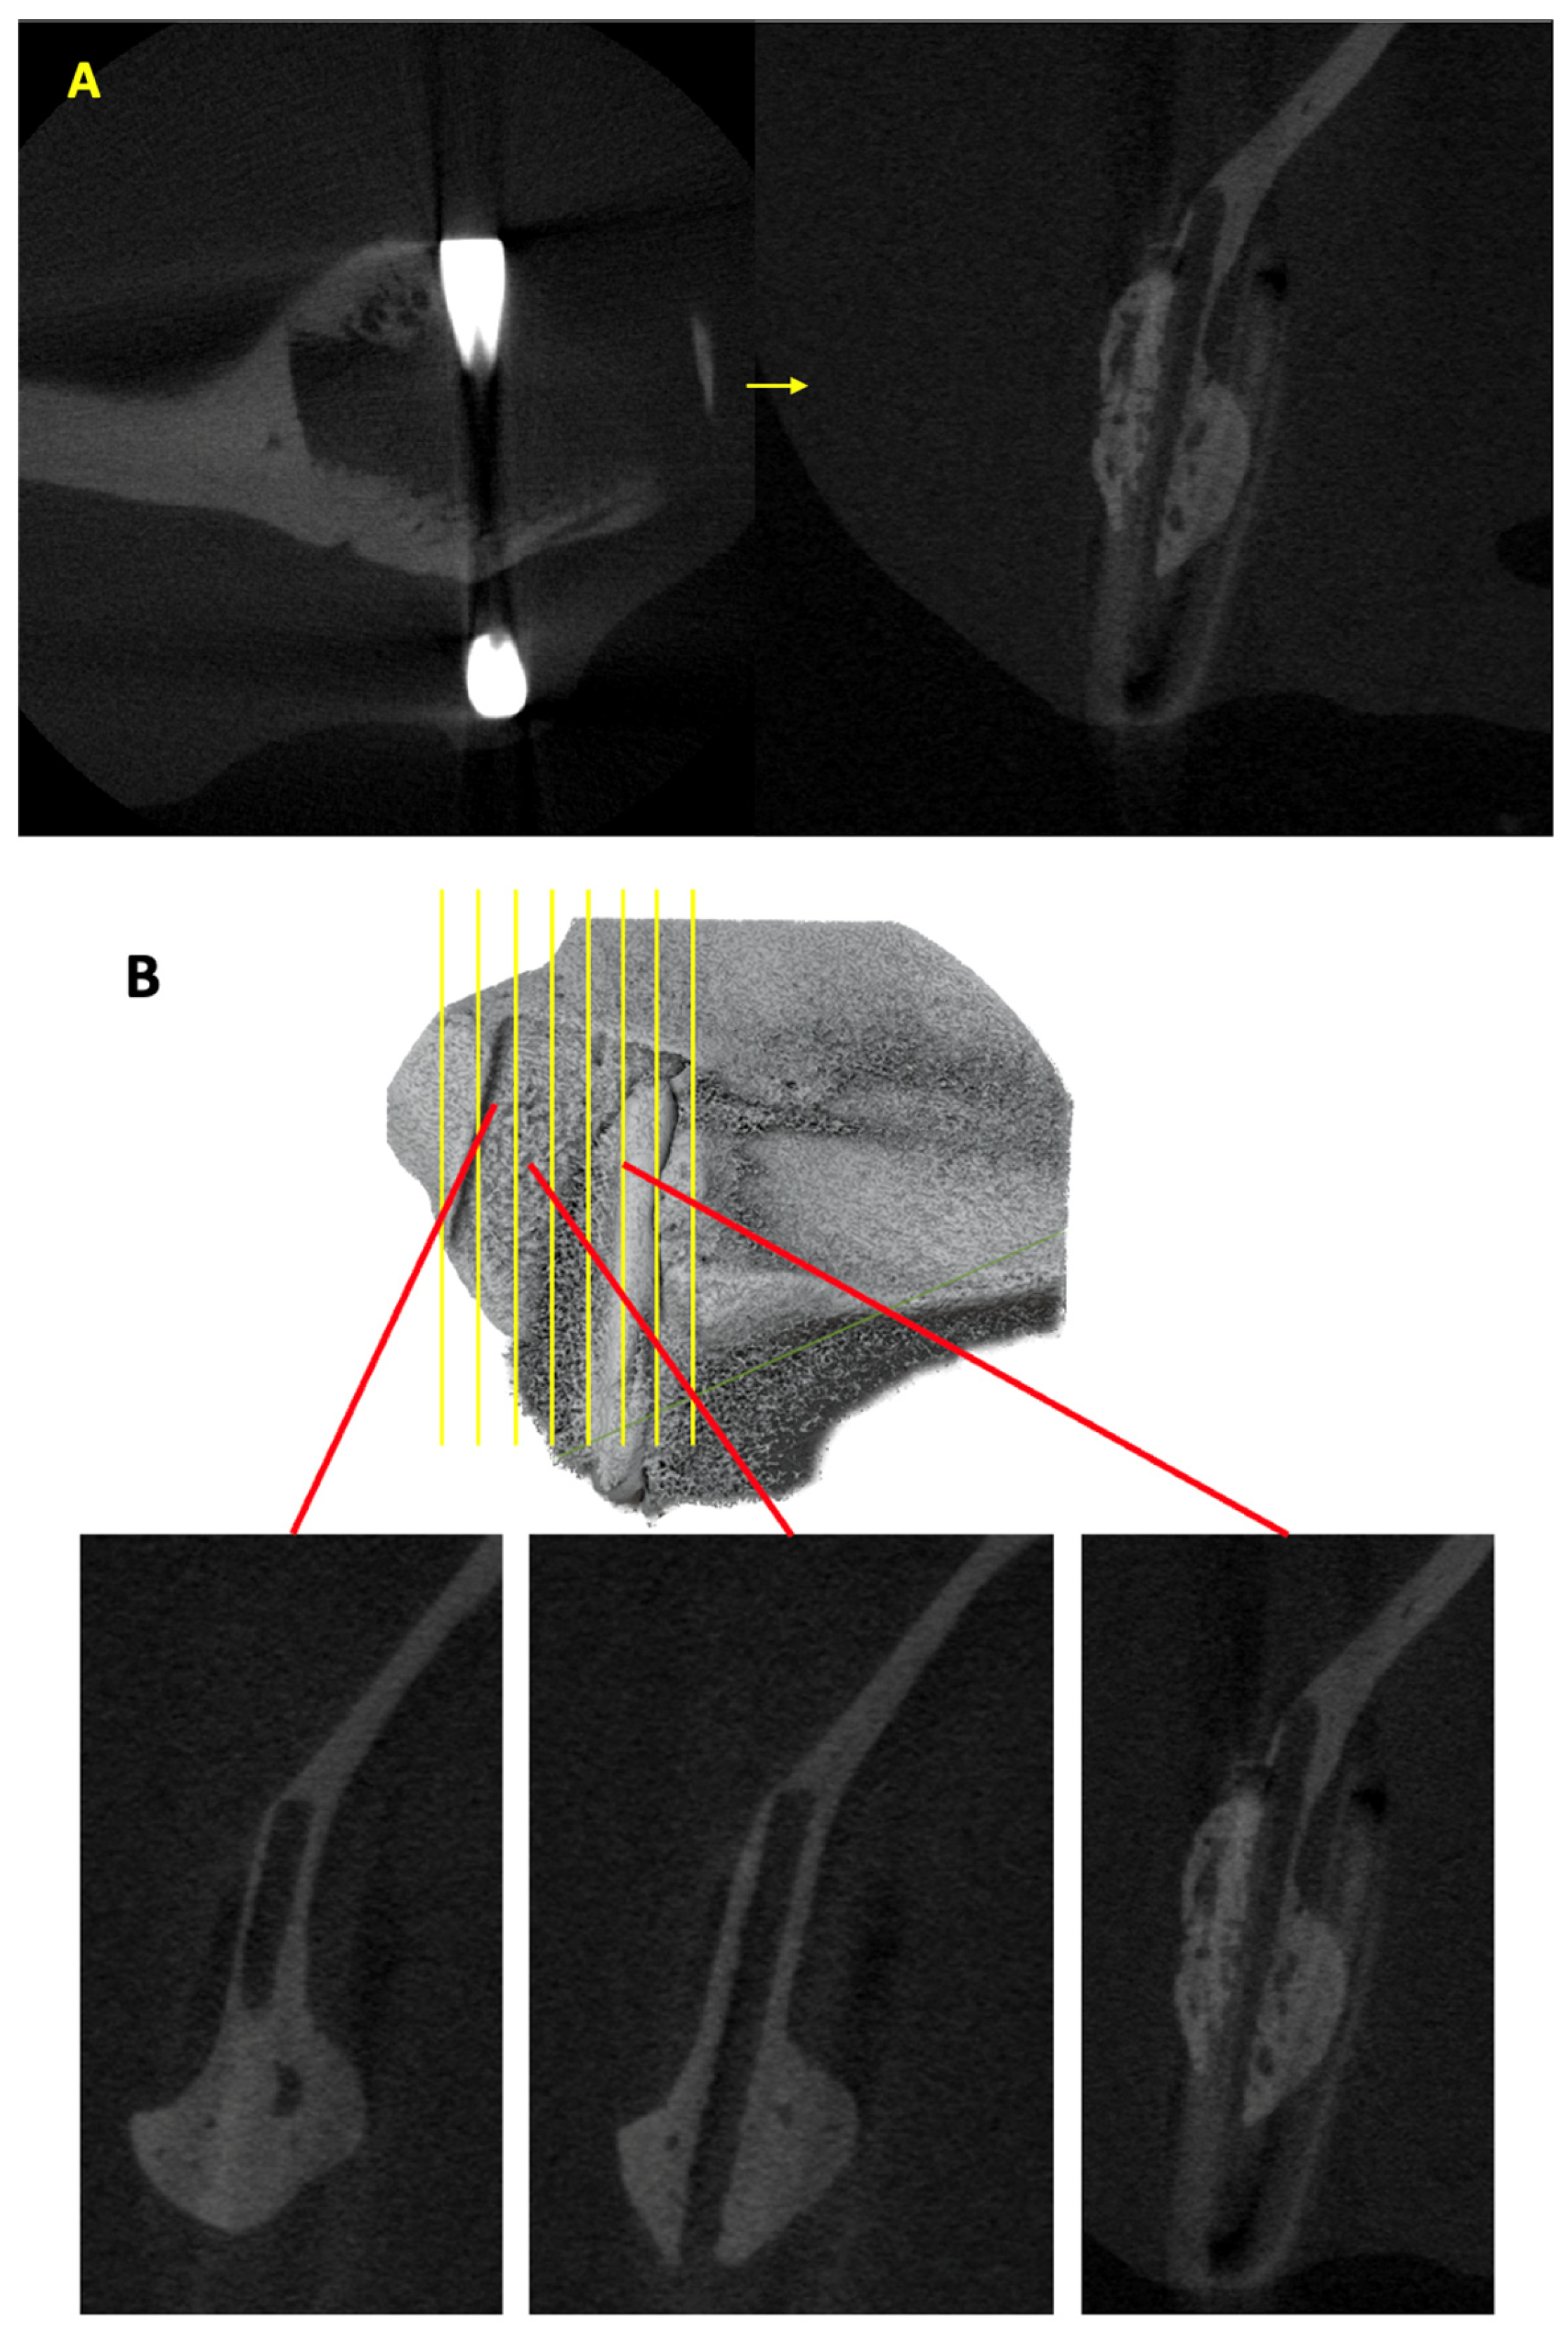

2.3. Assessment of New Bone Formation Using Micro-CT

3.1. Volume of New Bone Formed Outside Sheet